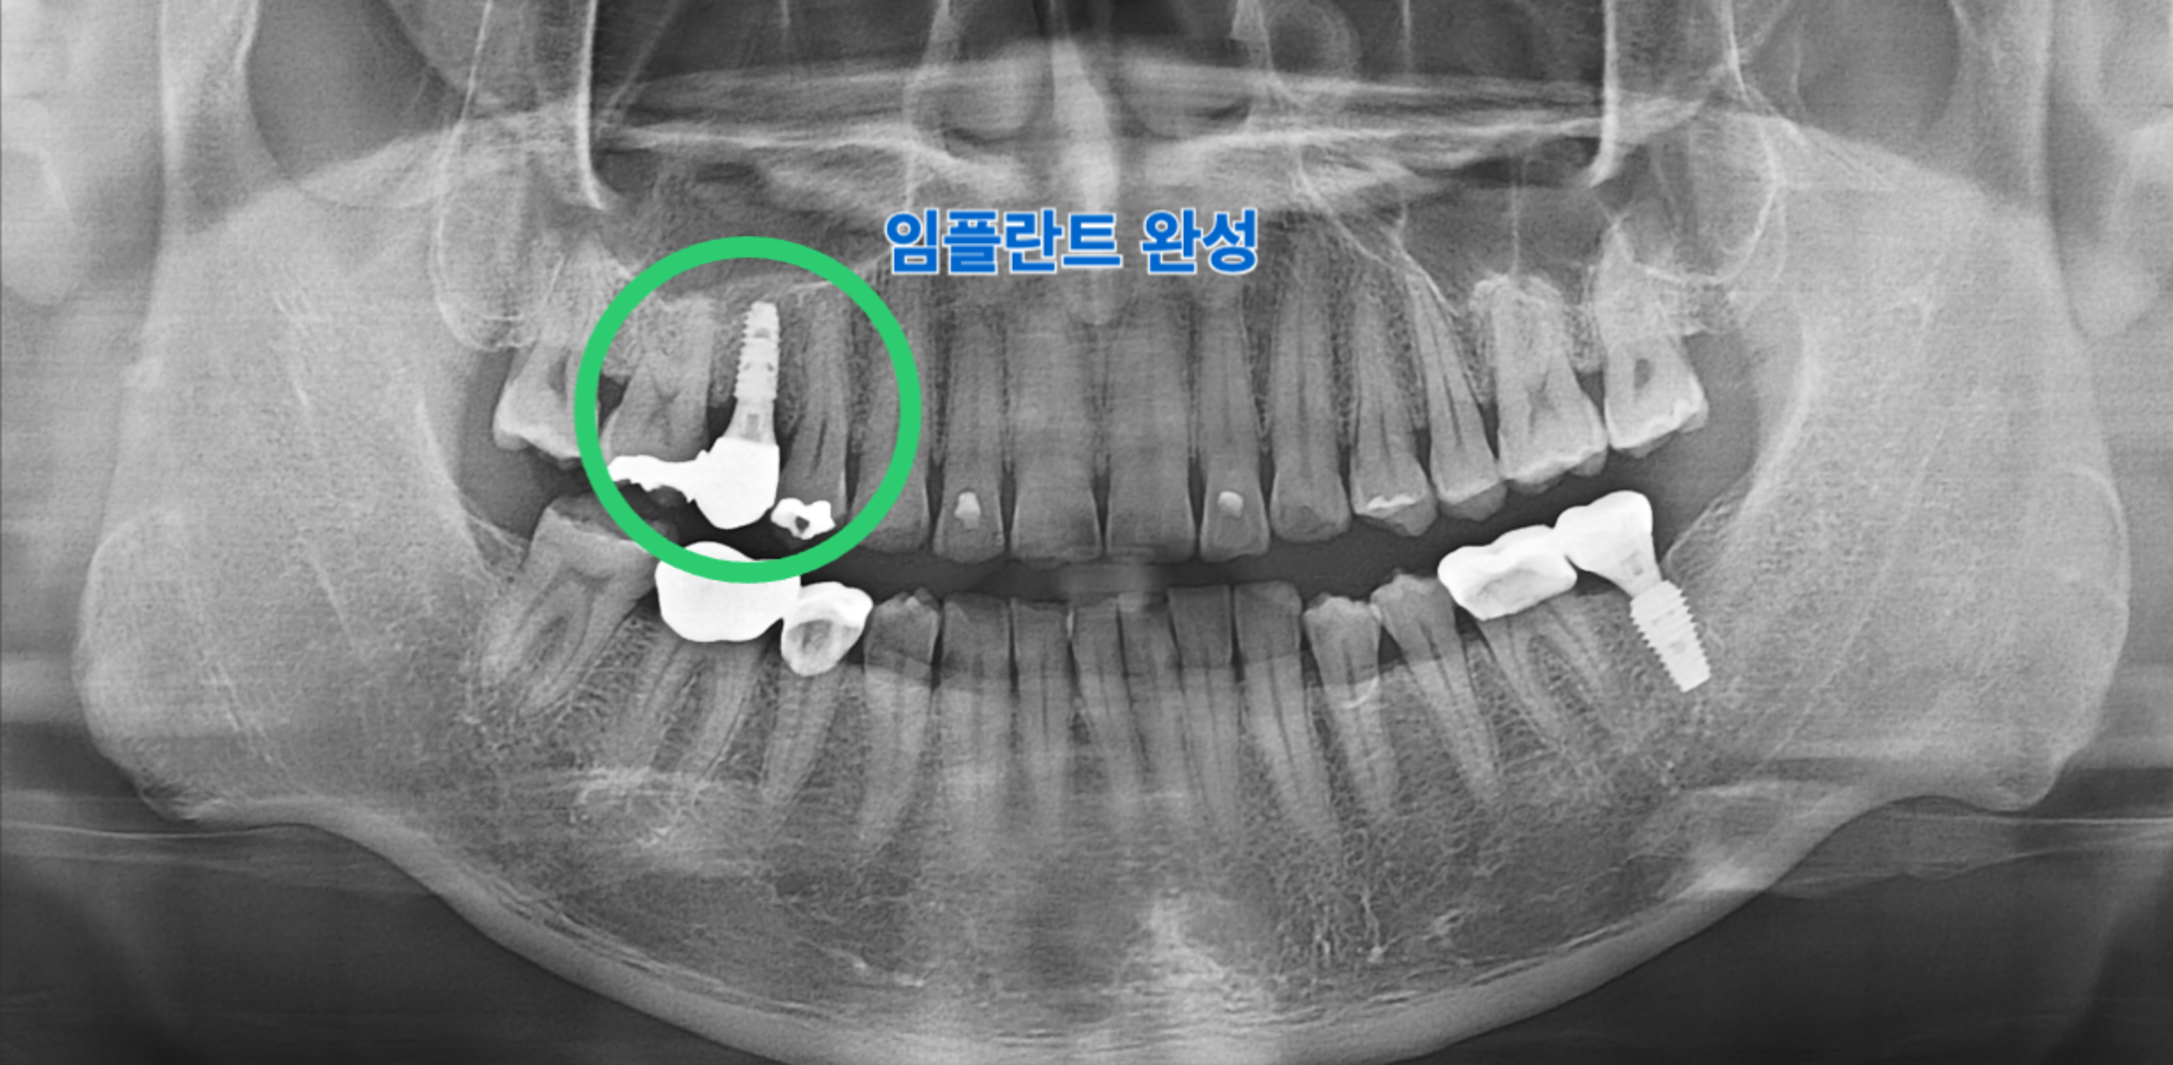

AFTER 15번 치아 임플란트 보철 완성

치료 후 : 15번 임플란트 보철 완성 (촬영일: 2026.02.11)

치아 보존이 불가하다고 판단하여 해당 치아를 발치하였습니다. 이후 상실된 치아의 기능을 대체하기 위해 임플란트 식립을 계획하고 진행하였습니다.

임플란트 식립 및 최종 보철 수복이 완료되었습니다. 이를 통해 상실된 치아의 기능적, 심미적 회복을 기대할 수 있었습니다.